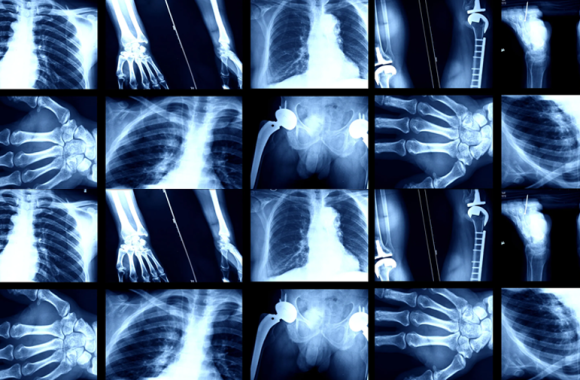

At MediCore Lab, we are at the forefront of transforming healthcare diagnostics through advanced imaging technologies. Ultrasound, a non-invasive and highly effective imaging method, uses high-frequency sound waves to create detailed visuals of internal organs and structures. This essential tool is invaluable for monitoring fetal development, diagnosing medical conditions, and guiding medical procedures.